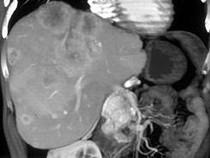

男,48岁,胃癌术后1年,未化疗,CT检查如图所示,最可能诊断为 ( )A.肝癌B.肝转移癌C.肝血管瘤D.肝脓肿E.肝囊肿

问题 男,48岁,胃癌术后1年,未化疗,CT检查如图所示,最可能诊断为 ( )

选项 A.肝癌 B.肝转移癌 C.肝血管瘤 D.肝脓肿 E.肝囊肿

答案 B